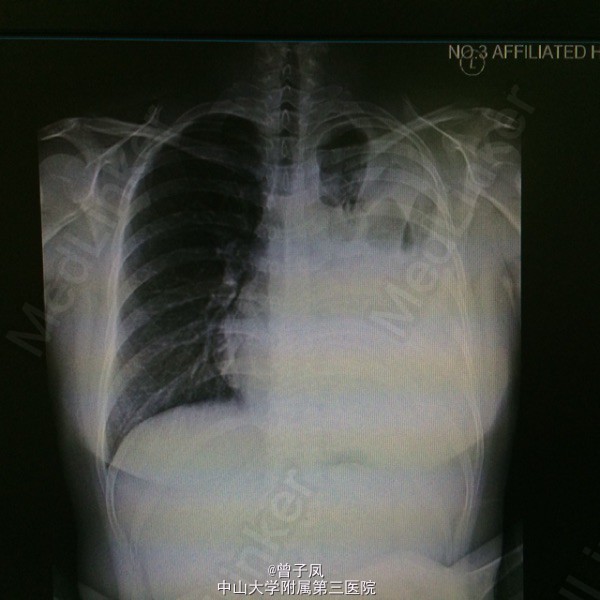

患者27岁女性,3月前曾行剖宫产术。 主诉:胸痛1周,咳嗽伴发热3天。 现病史:1周前无明显诱因出现左侧胸壁隐痛,深呼吸及咳嗽时明显,未重视。3天前出现咳痰、畏寒、发热,最高体温37度,后出现气促,间伴胸闷,至我院门诊查胸片示左侧大量胸腔积液,遂入院。

诊断:结核性渗出性胸膜炎,肺结核? 行胸腔闭式引流,引流出淡黄色液体,送胸水检查示渗出性,以淋巴细胞为主。复查胸片示胸水较前吸收后,查胸部CT示:考虑左肺浸润性肺结核并结核性胸膜炎,右下肺炎症。 予“异烟肼、利福平、乙胺丁醇”抗结核治疗,并与拜复乐抗感染治疗,辅以止咳治疗。